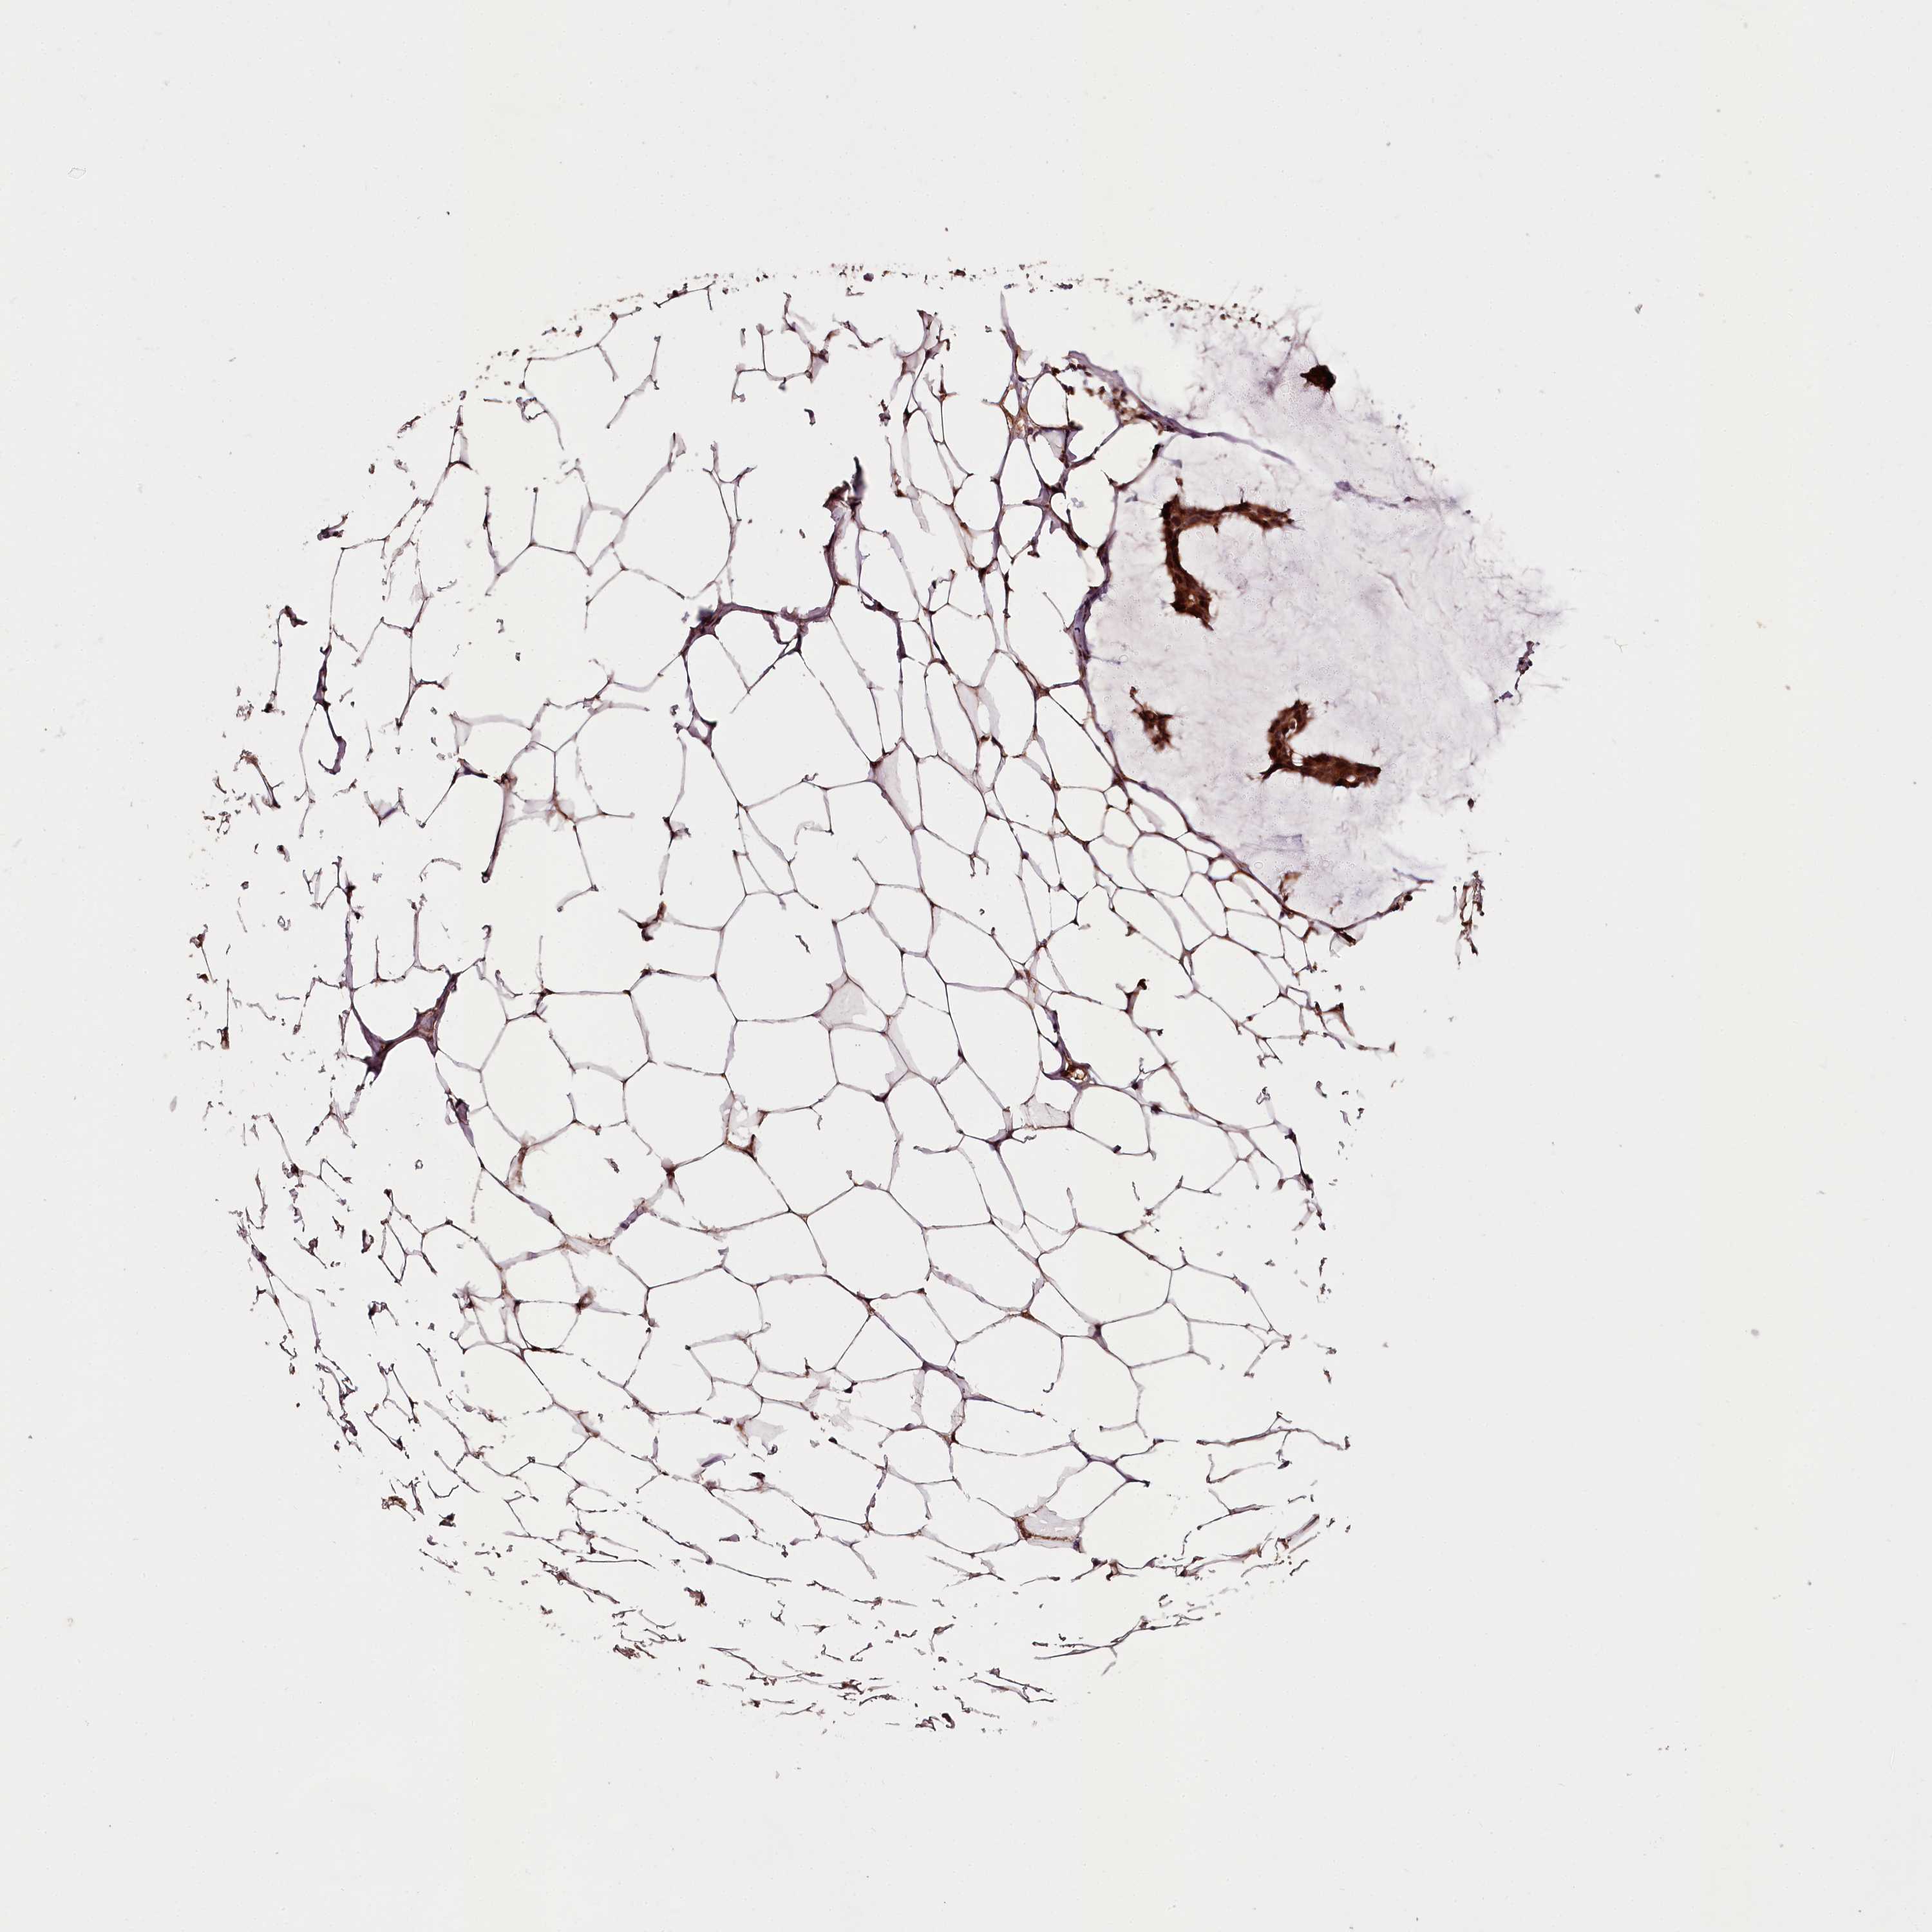

CANCER BREAST CANCER Show tissue menu

Breast cancer

Human cancer